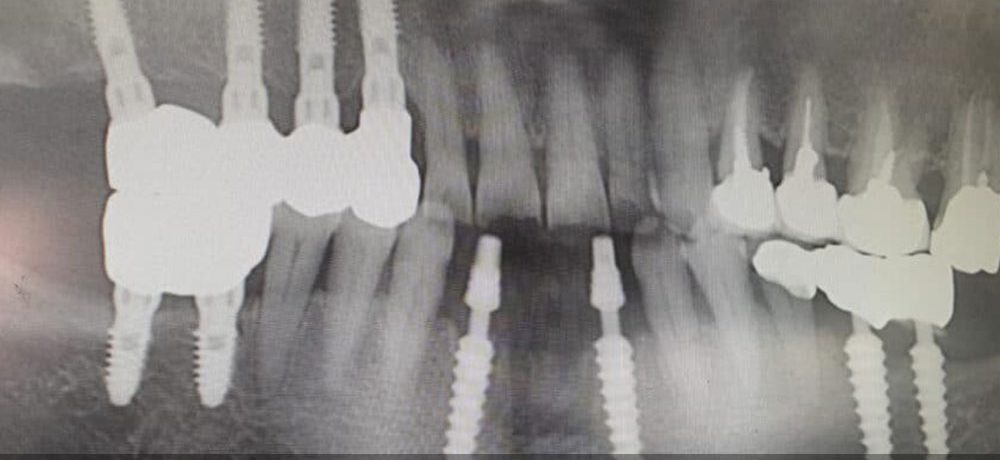

• تصاویر رادیوگرافی: در برخی موارد، دندانپزشک ممکن است نیاز به انجام تصاویر رادیوگرافی برای ارزیابی بهتر وضعیت ایمپلنت داشته باشد.

img